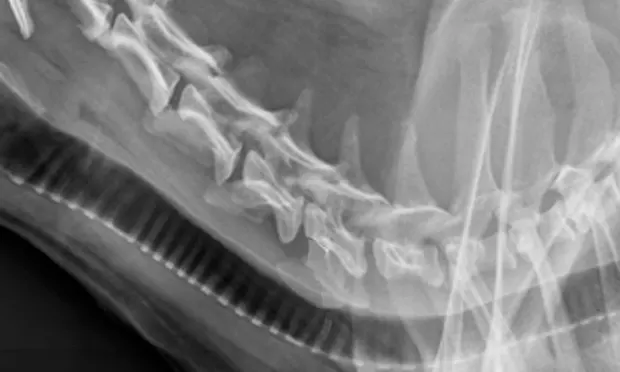

Figure 2. Lateral cervical radiograph demonstrating a collapsed disk space at C5-C6 (arrow).

CBC, serum biochemistry profile, and urinalysis results were within reference ranges. Thoracic and abdominal radiography disclosed no abnormalities. Radiographs of the cervical spine showed normal vertebral bone densities and soft tissue structures. The C5-C6 intervertebral disk space appeared narrow with some opacity within the canal (Figure 2).